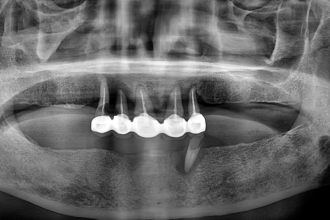

임플란트

굿프렌즈 치과 임상 케이스